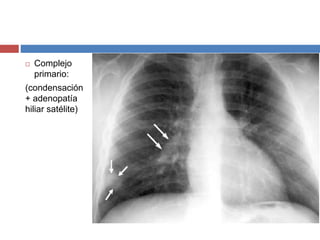

 Complejo

primario:

(condensación

+ adenopatía

hiliar satélite)

• #17 Complejo primario (condensación + adenopatía hiliar satélite): Esto se da en niños.